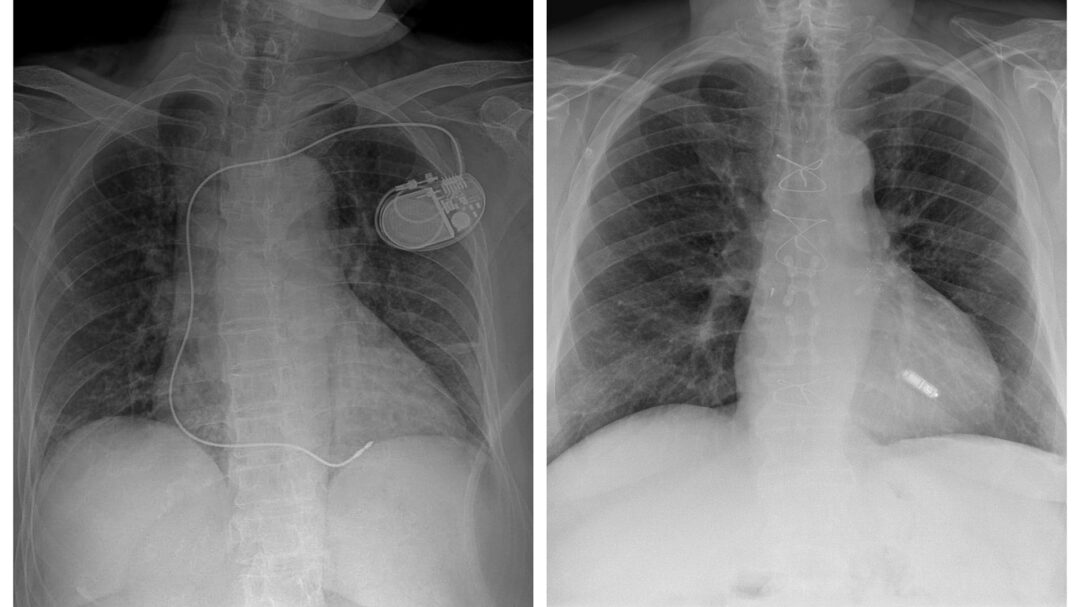

Ο πρώτος βηματοδότης, που εμφυτεύθηκε το 1958, αποτελείτο από πολλαπλά στοιχεία, μεταξύ των οποίων μια γεννήτρια παλμών με διάμετρο περίπου 7,5 εκατοστά. Ένας βηματοδότης νέας γενιάς διαθέτει γεννήτρια παλμών μεγέθους δύο κερμάτων του ενός ευρώ το ένα πάνω στο άλλο. Η συσκευή εμφυτεύεται υποδόρια κοντά στην κλείδα και συνδέεται με την καρδιά μέσω ενός ή περισσότερων εύκαμπτων καλωδίων τα οποία ονομάζονται ηλεκτρόδια (βλ. εικόνα). Όμως σήμερα υπάρχουν επίσης βηματοδότες χωρίς ηλεκτρόδια, οι οποίοι δεν είναι μεγαλύτεροι από μια κάψουλα πολυβιταμίνης – εξέλιξη που έχει μειώσει εντυπωσιακά τον κίνδυνο επιπλοκών από αυτές τις συσκευές.